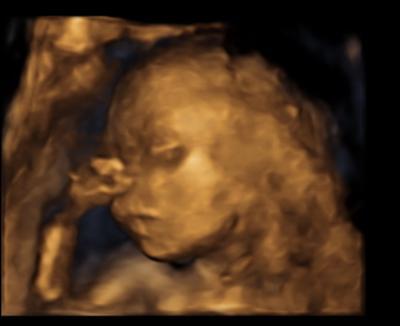

Hallo Ihr lieben ich schaue mir immer so gerne eure US Bilder an und da wollte ich euch auch mal unseren Kleinen vorstellen

Mei ist das ein schönes 3D Bild Da wird einem wieder bewusst das man einen richtig entwickelten Menschen unterm Herzen trägt. Manchmal wirkt mir das ganze noch so unreal, obwohl ich es immer treten spüre.. Aber bald bald ist es soweit und wir haben Ende März/Anfangs April - da purzeln die ersten

Ich gucke mir die Bilder auch total oft an um wirklich kapieren zu können dass der Kleine Mann in meinem Bauch sitzt wahnsinn so eine Schwangerschaft

Was ein tolles Bild! Menno ich will auch mal wieder ein 4d Bild kriegen

voll süß man kann sich echt verlieben in diese 3d bilder